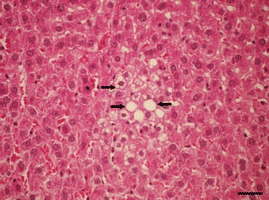

Fig. 1

Fig. 2

Fig. 3

Fig. 4

Fig. 5

Fig. 6

Fig. 7